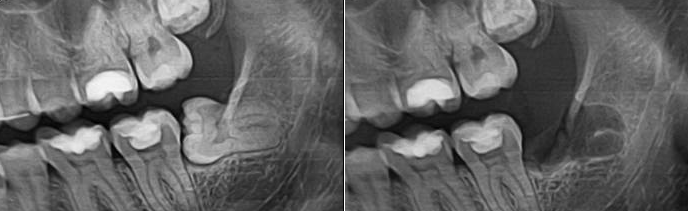

Удаление корня зуба: фото до и после